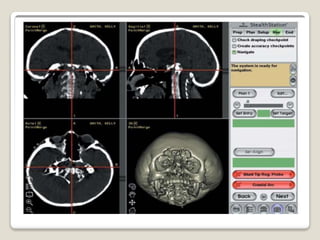

• 2 fundamental process

• Registration

• tracking

REGISTRATION

⚫ Once the pt is secured in OT table, registration of

cartesian coordinates of the CT scan to that pt is

done by:

 locating anotomical landmarks visible on the

pt and the image data using a probe that is

visible o the tracking device.

 The position of the tip of the probe is

identified by the tracking device and the

coordinates are fed back into navigation

software.

 other methods use masks and laser scanning

⚫ Calculations made in real time indicate the point

accuracy.

⚫ Some make use of fiducial markers that are applied

to the pt before scanning on the day of surgery.

⚫ Reference points should be adjacent to surgical field.

⚫ Registration error is only a measure of the accuracy

of correlation beetween selected points in the virtual

data sets and the anatomical markers identified on

the pt.

⚫ Target error:error that could be expected if a probe

was placed on a random point of interest in surgical

field.

influenced by the registration error

lessened if the target is within volume described

by fiducial markers.